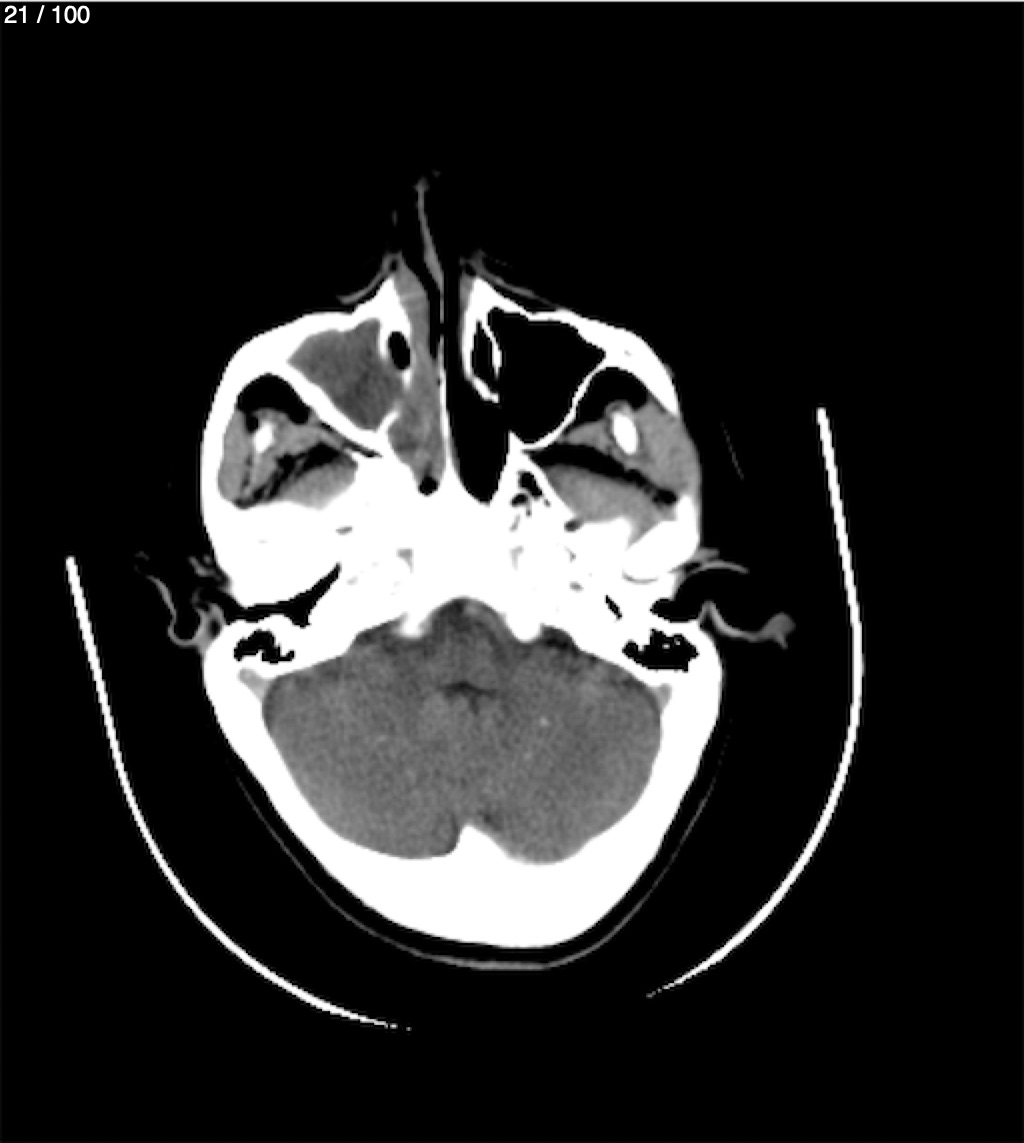

Valentin Perez Gomez 69A - T.C Craneo